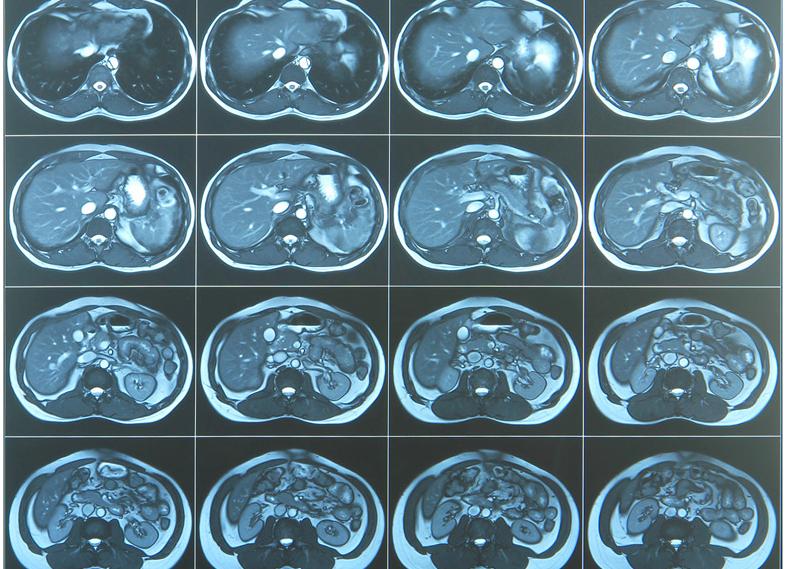

Простым и информативным способом оценки состояния ребенка в течение третьего триместра гестации, в первом (во время схваток) и втором (при потугах) периодах родов является мониторинг сердечной деятельности и сокращений матки матери. С какой недели делают КТГ? Исследование может проводиться с двадцать восьмой недели, но часто наиболее верные показатели удается получить только с тридцать второй недели. Это эффективный и безопасный метод диагностики, который не имеет противопоказаний, поэтому будущие мамы могут не волноваться ни о своем здоровье, ни о благополучии малыша.